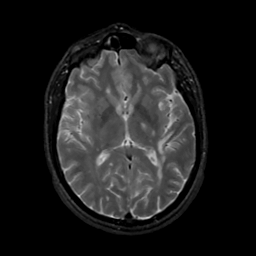

MR Study #10, April 28, 1991 -- Slice #26